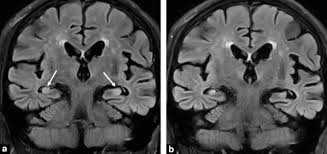

Differences In Mr Features Of The Substantia Innominata Between Dementia With Lewy Bodies And Alzheimer S Disease Semantic Scholar

Differences In Mr Features Of The Substantia Innominata Between Dementia With Lewy Bodies And Alzheimer S Disease Semantic Scholar from d3i71xaburhd42.cloudfront.net

Lewy, the scientist who discovered them. Loss of substantia nigra hyperintensity on 7 tesla mri of parkinson's disease, multiple system atrophy, and progressive supranuclear palsy. Besides nuclear imaging methods, the clinical utility of structural neuroimaging with magnetic resonance imaging (mri) for differential comparison between dementia with lewy bodies and alzheimer's disease. You also might see things that aren't there, called hallucinations. Lbd is a term that covers two conditions that have similar. Protein deposits, called lewy bodies, develop in nerve cells in the brain regions involved in thinking, memory and movement (motor control). Certain nuclear scans of the brain, including positron emission. How is lewy body dementia (ldb) diagnosed? Dr michael firbank discusses his study using functional mri in lewy body dementia and alzheimer's disease at the newcastle university institute. Focal atrophy in dementia with lewy bodies on mri: Memory loss is not always an early symptom. Lewy body dementia (lbd) is a type of progressive dementia. Many people also experience changes in alertness including daytime sleepiness, confusion or staring spells.

The lewy body society (see end of leaflet) is a registered uk charity which has a website full of information. Dementia with lewy bodies or lewy body dementia is dementia caused by the presence of lewy bodies in the brain. Loss of substantia nigra hyperintensity on 7 tesla mri of parkinson's disease, multiple system atrophy, and progressive supranuclear palsy. Also, there is a helpline for support provided by dementia. It is reported as the second most common form of dementia following alzheimer diseas.